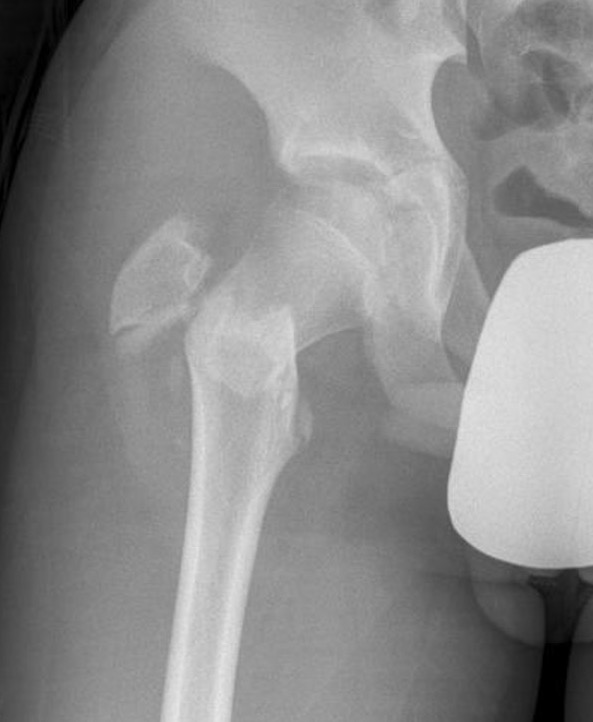

Delbert Classification

Type 1

- transepiphyseal separation / fracture

- rarest

- associated with hip dislocation

- AVN 100%

Type 2

- transcervical fracture

- commonest 50%

- AVN 50%

Type 3

- basicervical

- second most common 30%

- AVN 30%

Type 4

- intertrochanteric fracture

- AVN 10%